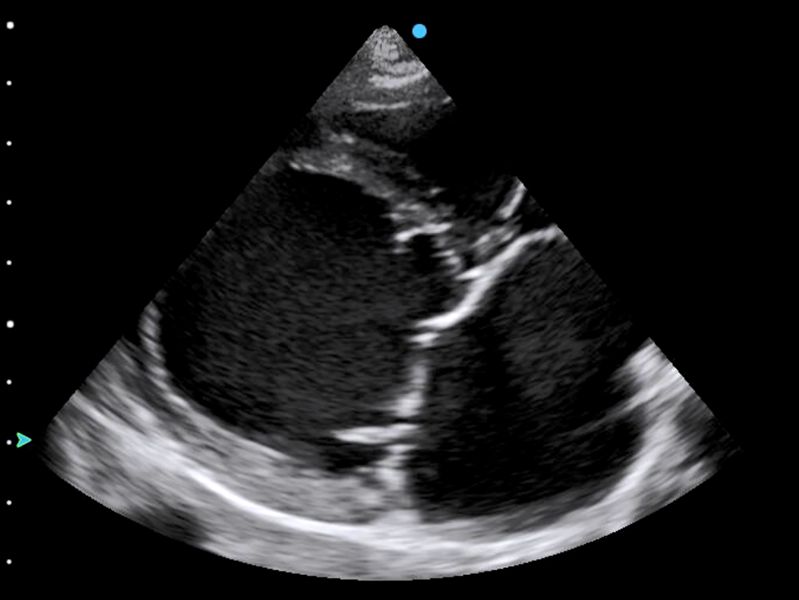

The left atrium can dilate due to volume overload, pressure overload, or both. The left atrium does not always dilate uniformly in all directions, so it is important to consider other views besides the short axis. In the previous example, left atrial enlargement was obvious even from the right parasternal long axis view. Can you spot the cause from the video below?

Above: DCM dog with a very dilated left atrium